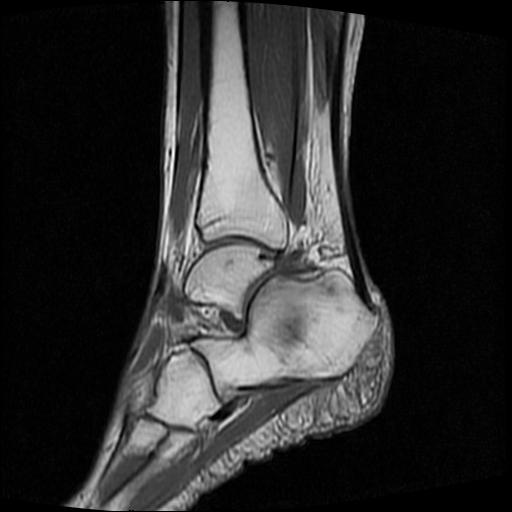

标题: MRI0968:女性,70岁,跟骨信号异常 [打印本页]

标题: MRI0968:女性,70岁,跟骨信号异常

女性,70岁,右侧跟骨疼痛2个月,负重时加剧,不负重时不疼。

胫骨下段,跟骨、距骨可见斑片状异常信号区;考虑:转移瘤

跟骨长t1长t2信号异常,边缘模糊(肿瘤一般边界清楚,故肿瘤不考虑),压脂像呈高信号--骨髓水肿(炎症?)。